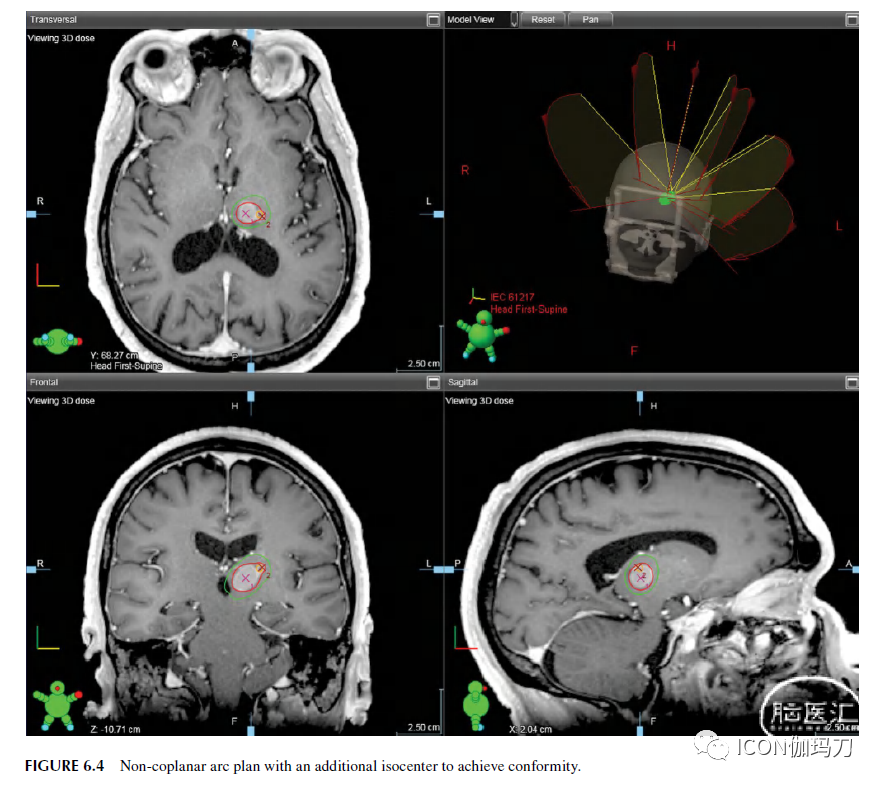

适形性度量范围从0到1,其中1为最佳情况。如图6.4所示,为了避免不规则靶区出现冷点,增加了一个5毫米的锥体。由于等剂量云团与两个锥状体重叠,这一平面将比单一等中心平面产生更高的热点(an additional 5-mm cone was used to avoid a cold spot at the corner of this irregular shaped target. Because the isodose clouds overlap from the two cones, this plan will generate a higher hot spot than a single isocenter plan.)。在这种情况下,适形性是以牺牲不均匀性为代价的(conformity is achieved in the sacrifice of inhomogeneity)。

图6.4非共面拉弧计划,增加等中心以达到适形性。